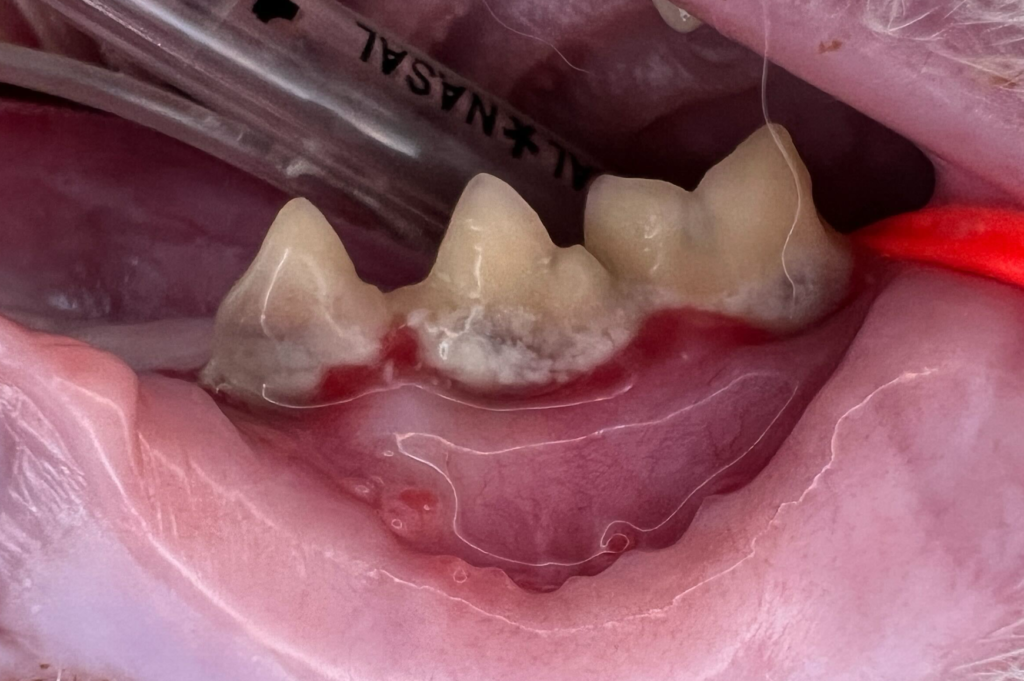

見た目では歯がしっかりしているように見えても、歯科用レントゲンを撮ると歯が根元から溶けていることがはっきり分かります。

吸収病巣(FORL:Feline Odontoclastic Resorptive Lesions)は、歯の表面や根の部分が少しずつ溶けていってしまう病気です。

当院では、歯科用レントゲンで状態を確認し、必要に応じて部分的あるいは全体的に抜歯を行います。

外からは分かりにくいため、レントゲン検査で初めて診断できるケースが多いのが特徴です。